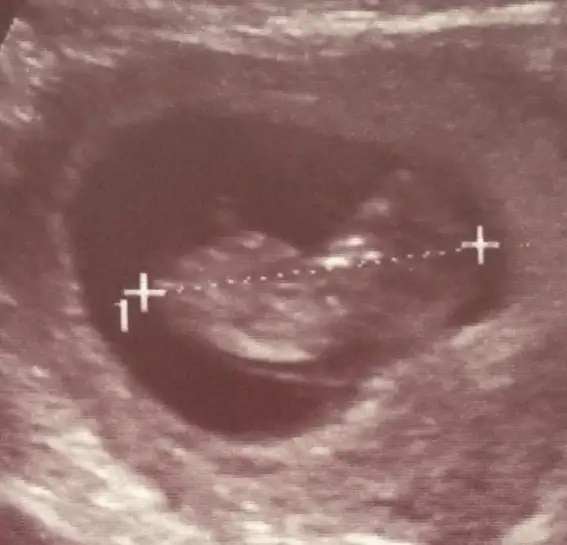

Eki Görüntüle 473831 simdi burada cikintilara bakin eger bel popo cizgisine paralel ise kiz

yok 30 derecelik bir aciyla yukari bakiyorsa erkek

kiz nublarinida koyacagim

Eki Görüntüle 473837 bu benim kizim cikinti gayet net ve ortada ve ben kizim diyooo